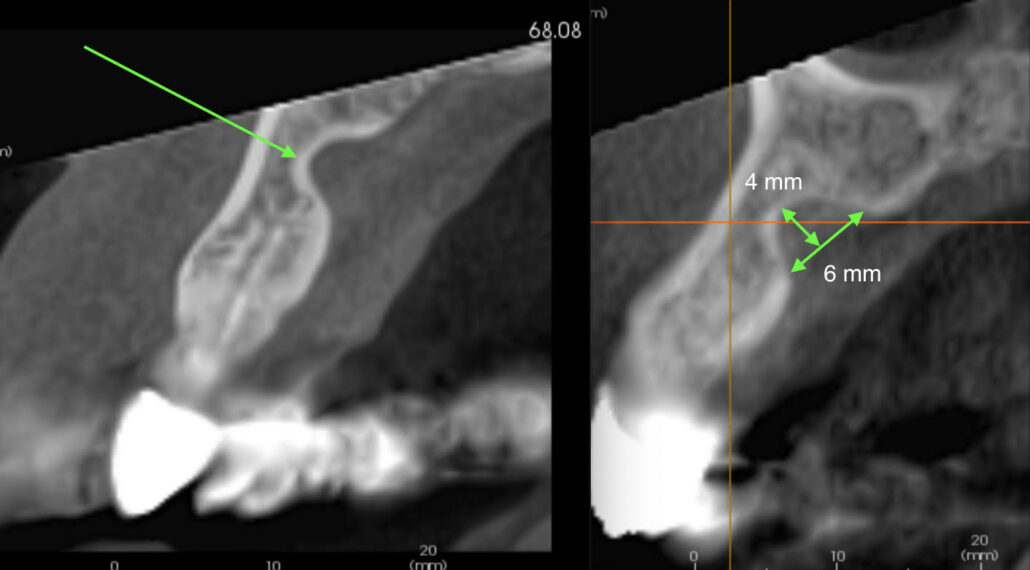

Two reconstructed CBCT cross sectional alveolar arch images made 6 months apart. The left is pre-extraction UL2 and the right 6 months later, post extraction UL2. Notice that both images have a well defined corticated concavity in the palatal side of the alveolar bone ridge approximately 4 mm wide by 6 mm deep. A detailed examination of cross sectional slices across the concavity confirmed that the bone concavity had not changed over a 6-month time interval.

- The large well defined corticated bone concavity palatal to the apex of UL2 is a Stafne bone cavity. These are benign developmental defects that occur more frequently in men, 6:1 male:female, usually in the posterior mandible on the lingual surface and inferior to the mandibular canal. They usually contain fat, salivary gland or vascular tissues. However, I have seen them in the anterior mandible across the midline lingual region and now in the palate. As long as they remain well corticated and do not increase in size they do not require treatment. Another CBCT just of the anterior maxilla region should be made 6-12 months after the first discovery or sooner if there are signs or symptoms. Providing no change is observed, no further monitoring is required.